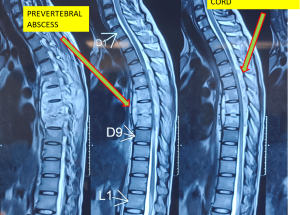

Expert spine services including minimally invasive surgery, pain management, and deformity correction.